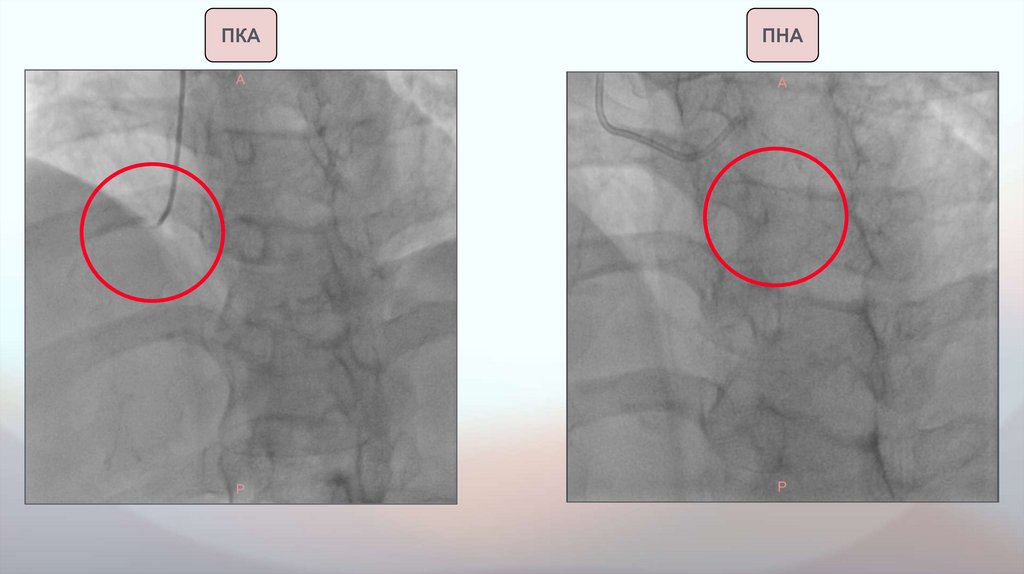

Данные инструментальных исследований. Коронароангиография.

Коронароангиография от

24.11.2025:

Правая коронарная артерия

(ПКА): значимый стеноз в

проксимальном сегменте.

ФРК ПКА: iFR - 0,70, FFR - 0,65

(значения iFR < 0,89 и FFR <0,80

- гемодинамический значимый

стеноз)

Передняя нисходящая артерия

(ПНА): в среднем сегменте

стенозирована на 60-70%, далее

с неровными контурами.

Остальные КА с неровными

контурами - начальные

атеросклеротические изменения.

ПКА

ПНА